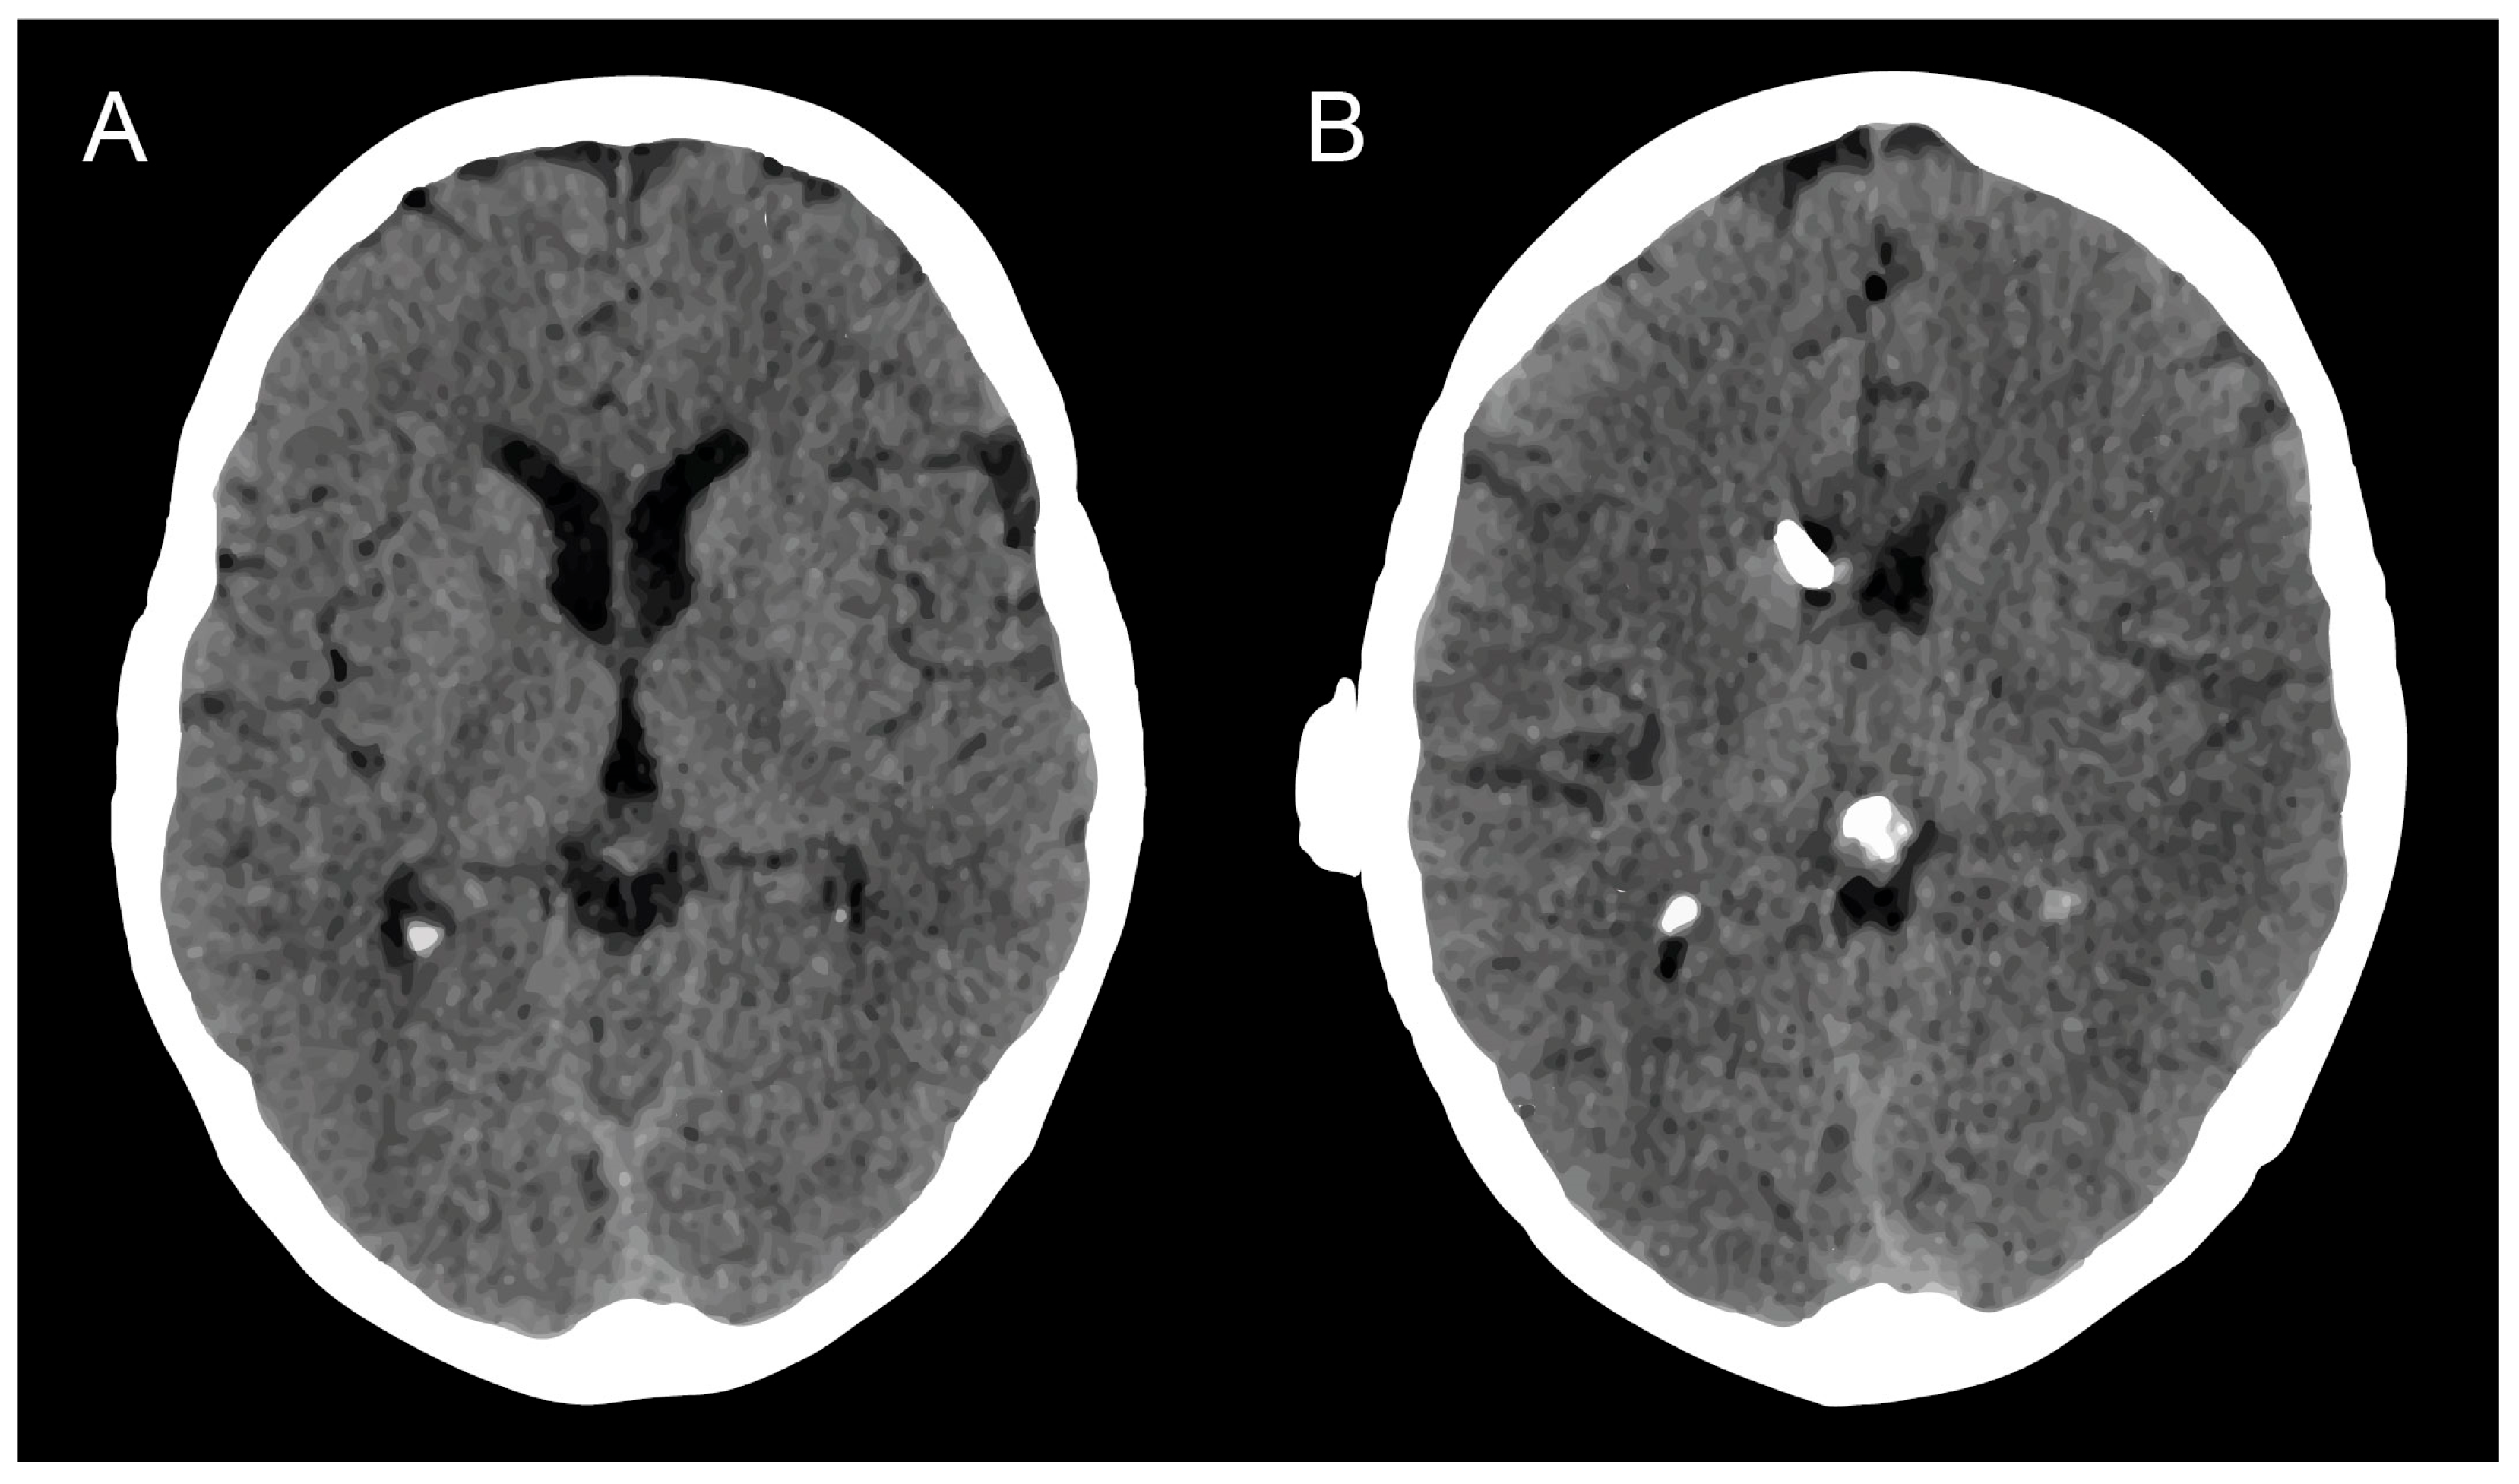

3.2. Hydrocephalus

3.3. Surgical Management of mS/R